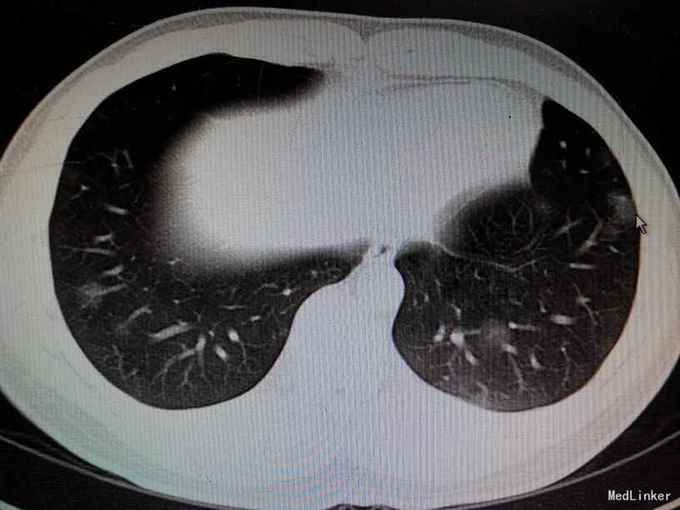

患者青年男性,21岁,因“痰中带血46天”入院。患者于08-26无明显诱因出现痰中带血,量较少,鲜红色,偶有血凝块,无发热、咳嗽,无胸闷胸痛,无呼吸困难,无盗汗等不适,09-02至XX医院就诊,查胸部CT示“两肺炎症首先考虑,结核可能待排”;血常规、肿瘤标志物全套、真菌G、GM试验,隐球菌乳胶凝集试验,T-SPOT,HIV等均阴性,肺吸虫抗体阴性,抗核抗体全套正常;9-14气管镜检查示“左上肺管壁黏膜出血伴左下肺背段管口血液储留”;9-18行右肺活检,术后病理示“少量肺泡组织,部分肺泡间隔稍增粗,纤维组织增生,局部见淋巴细胞浸润,另见少量纤维素渗出”。予左氧氟沙星、阿莫西林克拉维酸钾抗感染治疗30余天,止血等对症治疗,症状未见明显好转。9-28辅查胸部CT示双肺病灶较前增多,复查血常规、血生化等未见明显异常。建议转入我院,进一步明确咯血性质。

讨论:本例是年轻患者,反复不明原因痰中带血,胸部CT示双肺弥漫肺泡出血,外院抗感染疗效不理想,患者无感染的临床表现,影像学表现不像真菌等非特异性感染,考虑非感染性疾病可能性大,其影像学符合过敏性疾病表现,且患者IgE升高。同时也可能是寄生虫感染或自身免疫性疾病,但肺吸虫抗体阴性,建议可复查,同时查血吸虫抗体,自身免疫方面,因自身抗体全套均阴性,考虑可能性较小。分享这个病例,也想听听大家的意见。